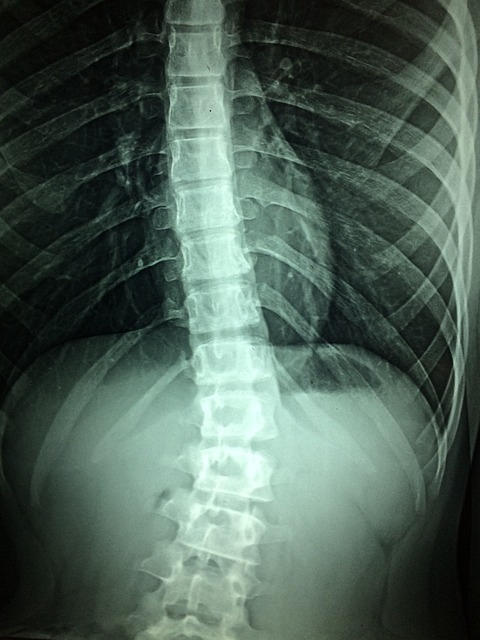

척추협착증의 증상은 다음과 같습니다:

척추협착증은 다양한 원인으로 인해 발생할 수 있습니다: